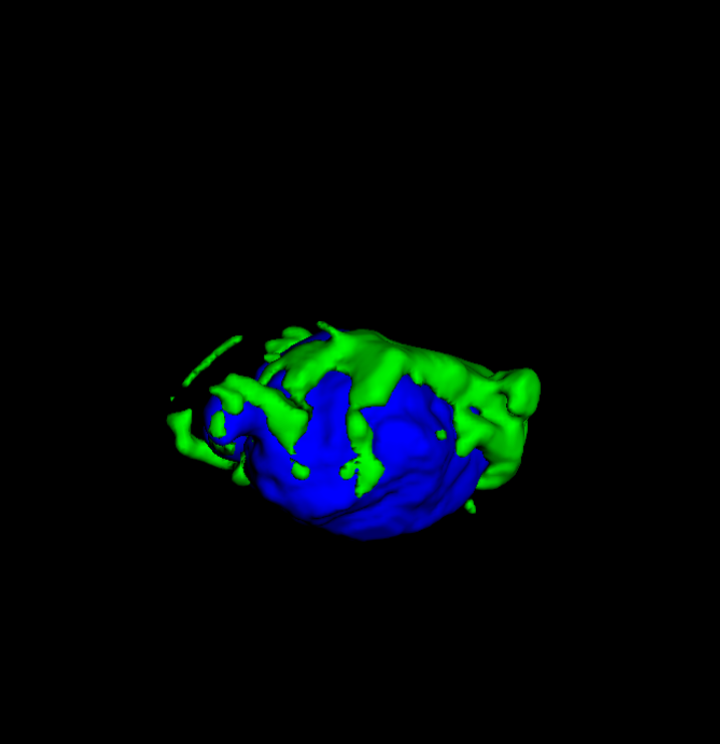

| Input | 3D Tumour | |||

![]() |

Tumour Information Preservation. For the brain tumor segmentation, we use a Swin UNETR model[27, 70], trained with random rotation, and intensity as data augmentation. In Figure 5, we highlight the tumor profiles of the generated MRIs compared to the ground truth tumour profile. In the test set with human ground-truth annotations (), the real MRI Dice score is 85.15 while the generated MRIs from a single slice have a dice score of 83.09. This shows how the generated MRIs indeed preserve the tumor information and can act as an affordable and informative pseudo-MRI, before conducting an actual costly MRI examination in hospitals.

B.4 Tumour Information Preservation

On the test set with human ground-truth annotations (), the brain volumes generated from single slice input preserve the volume of the different tumour components (paired t-test, for all 3 classes) (see Table 3). The real MRI Dice scores are put for reference to our generated MRIs. X-Diffusion outperforms baselines TPDM [36] and ScoreMRI [18] in tumour preservation (see Table 3 and Figure 12). We ran experiments comparing the tumour segmentation Dice Score varying X-Diffusion configurations. The multi-slice input X-Diffusion achieves a marginally better Dice Score than the single-slice input model (83.47 83.09). We also ran experiments with slice input used for volume reconstruction intersecting or not with tumour. We observe on average a drop of 6% Dice Score (see Table 3). Further away from the tumour the input slice for volume reconstruction is selected, and we observe a linear decrease in tumour segmentation Dice Score with the lowest value of 77.21 Dice Score (see Figure 15).